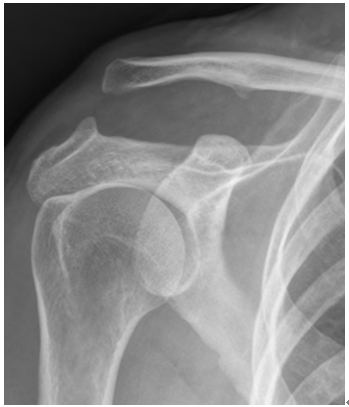

영상 진단

X-ray: AC 관절의 탈구 정도와 쇄골의 위치를 확인합니다. X-ray는 쇄골과 견봉 사이의 거리 증가를 보여줄 수 있습니다.

MRI 또는 CT 스캔: 더 자세한 이미지가 필요한 경우에 사용됩니다. 이는 연조직 손상의 정도를 평가하는 데 유용할 수 있습니다.